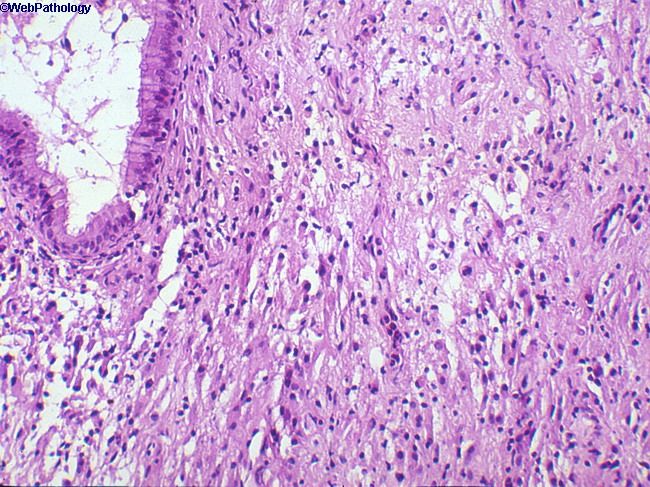

Гистологическое строение опухоли

Гистологическое строение опухоли 110 фотографий